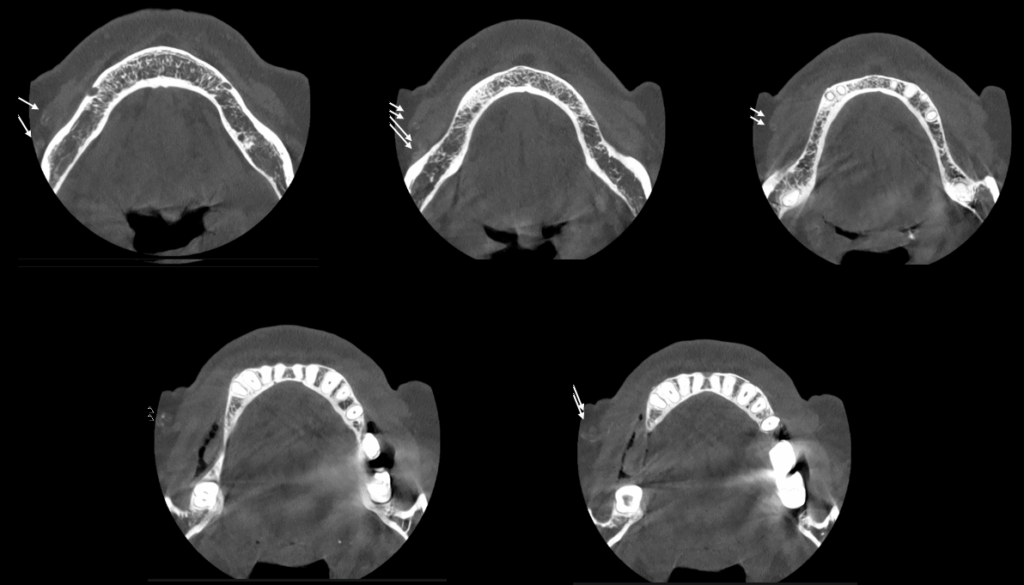

A la evaluación de la tomografía volumétrica (cone beam) bimaxilar en los cortes axiales (Figura 2) y transaxiales (Figura 3) se observa una imagen hiperdensa tubular de trayecto serpentiginoso con recorrido desde escotadura antegoneal al espacio bucal de lado derecho compatible con mineralización de tejidos blandos.

CORTES AXIALES